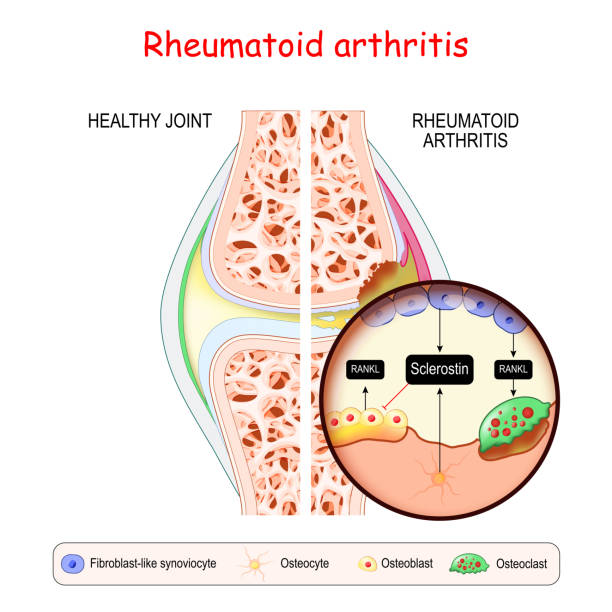

- Rheumatoid Arthritis (RA):

- It is an autoimmune condition where the body’s immune system attacks the lining of joints.

- Common symptoms are swelling, warmth, and tenderness in the hip joint, morning stiffness lasting over an hour.

- It hurts when the inflammation damages joint cartilage and bone, eventually leading to joint deformity.

- It often affects both hips symmetrically.